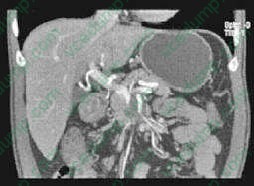

You are about to see a 52-year-old man in your office who presented with a 30-lb weight loss over the past 3 months and jaundice. He also has begun to develop early satiety and frequent vomiting. You had obtained a CT scan, which is shown in Figure 2-11. After reviewing the results of the scan, you discuss the diagnosis with him. He becomes angry and he demands that you operate immediately to remove the tumor. In response you do which of the following?

D. Calmly review the diagnosis with the patient and help console him and his family before reviewing the options for management including potential clinical trials. explanation:

Informing a patient of a new diagnosis of cancer can be a very challenging and emotional experience for both the patient and the physician. It is important to maintain composure and not to rush. Certainly in the setting of a terminal cancer, the news can be devastating. The discussion that will follow this kind of information will often be lost as the patient copes with the news. In these situations, it is important to give the patient time to grieve. It is also important to be prepared to spend adequate time with the patient and family in order to review any questions. Finally, it is not unreasonable, if the patient is in agreement, to give them time to process this information and to discuss the diagnosis with their family before presenting them with management options. It is poor practice to avoid these confrontations, and a new diagnosis of cancer should be presented to the patient by a physician in a face-toface manner if possible. It is also important to have information for the patient to take home in the form of handouts, pamphlets, or Internet resources, in order to help them continue to come to terms with the diagnosis and the current management options that are available.